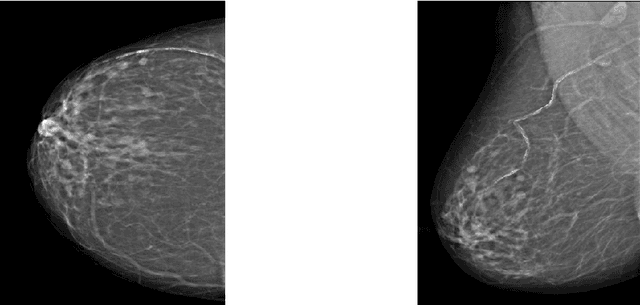

Abstract:Breast cancer is the second leading cause of cancer-related death after lung cancer in women. Early detection of breast cancer in X-ray mammography is believed to have effectively reduced the mortality rate. However, a relatively high false positive rate and a low specificity in mammography technology still exist. In this work, a computer-aided automatic mammogram analysis system is proposed to process the mammogram images and automatically discriminate them as either normal or cancerous, consisting of three consecutive image processing, feature selection, and image classification stages. In designing the system, the discrete wavelet transforms (Daubechies 2, Daubechies 4, and Biorthogonal 6.8) and the Fourier cosine transform were first used to parse the mammogram images and extract statistical features. Then, an entropy-based feature selection method was implemented to reduce the number of features. Finally, different pattern recognition methods (including the Back-propagation Network, the Linear Discriminant Analysis, and the Naive Bayes Classifier) and a voting classification scheme were employed. The performance of each classification strategy was evaluated for sensitivity, specificity, and accuracy and for general performance using the Receiver Operating Curve. Our method is validated on the dataset from the Eastern Health in Newfoundland and Labrador of Canada. The experimental results demonstrated that the proposed automatic mammogram analysis system could effectively improve the classification performances.